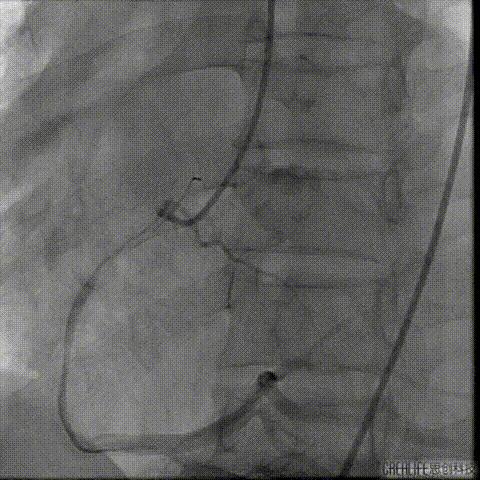

导丝跨瓣及测压

导丝跨瓣后测得跨瓣压差

升主动脉压104/36mmHg

左室压145/15mmHg

跨瓣压差41mmHg

此时患者出现室速 血气提示代谢性酸中毒、高钾血症,予电复率、补碱、补镁、碘氨酮等治疗后恢复窦性心律。